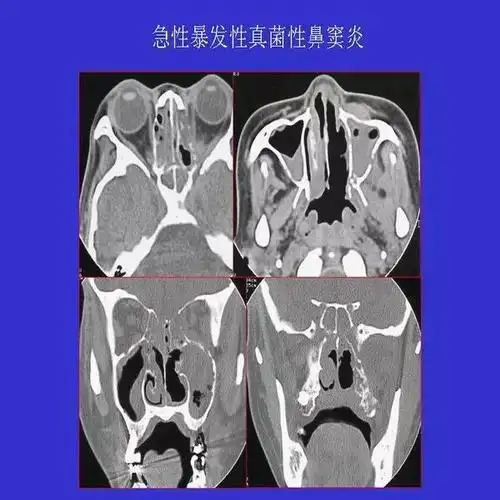

真菌性鼻窦炎影像学诊断

真菌性鼻窦炎